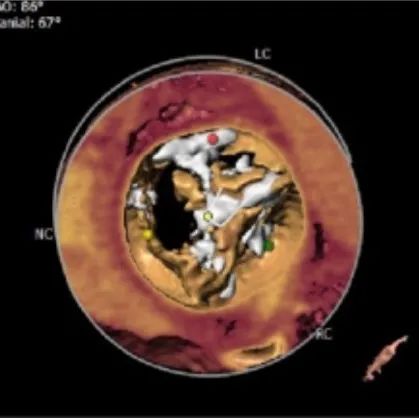

主动脉根部测量:

ANNULUS

SOV DIAMETER

LVOT

STJ

ASCENDING AORTA

LEFT VENTRICLE

钙化分布

HU542钙化积分1364mm³

左心室影像

心室壁增厚